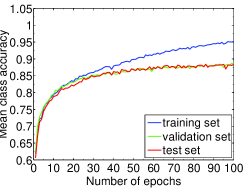

We highlight that training-relevant hyper-parameters can significantly affect the convergence of cost function, the learning speed and the generalization capability of the network. Their impacts are demonstrated via the learning curves of MCA on training, validation and test sets shown from Fig. 4 to Fig. 8. In each figure, we focus on one hyper-parameter while the others are set to their optimal values in Table 2.

In sum, among the hyper-parameters of a CNN, the learning rate, mini-batch size, momentum coefficient, and weight decay coefficient can significantly impact the network training process. They have to be carefully tuned before satisfactory classification performance is obtained. For our deep CNN system, with the hyper-parameters set in Table 2, we can achieve the MCA of % on the test set of ICPR2014 dataset without using data augmentation.